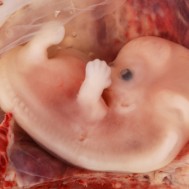

Baby: Week 7

At week 7 all essential body parts are present and accounted for!

All essential body parts are present and accounted for. Your ankles have formed, your arms are long and bend at the elbows. With basic physiology in place, rapid growth and weight gain are the next steps![1]

You are intricately detailed, but still so tiny, only about 3/4 inch (20 millimeters) long.[2]